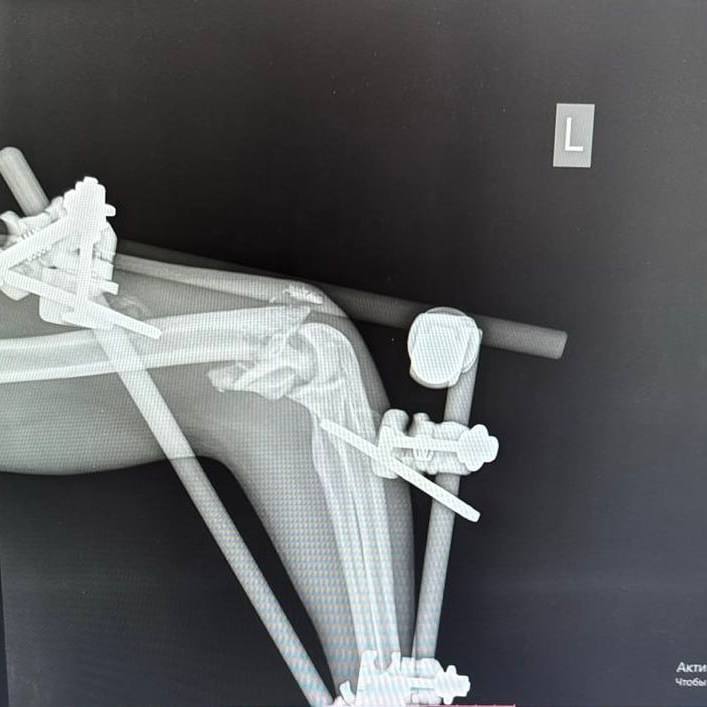

После обследования пациента экстренно прооперировали. Пациенту диагностировали множественные переломы костей лица, рёбер в нескольких местах, правой и левой плечевых костей, седалищной кости и правой голени. Правое лёгкое оказалось разорванным, в плевральной полости скопились воздух и кровь. В ходе операции пациента стабилизировали, установили аппараты внешней фиксации и перевели в реанимацию травмоцентра.

В течение месяца пациенту провели пять операций остеосинтеза. Хирурги поэтапно возвращали смещённые костные отломки в правильное анатомическое положение и фиксировали их.